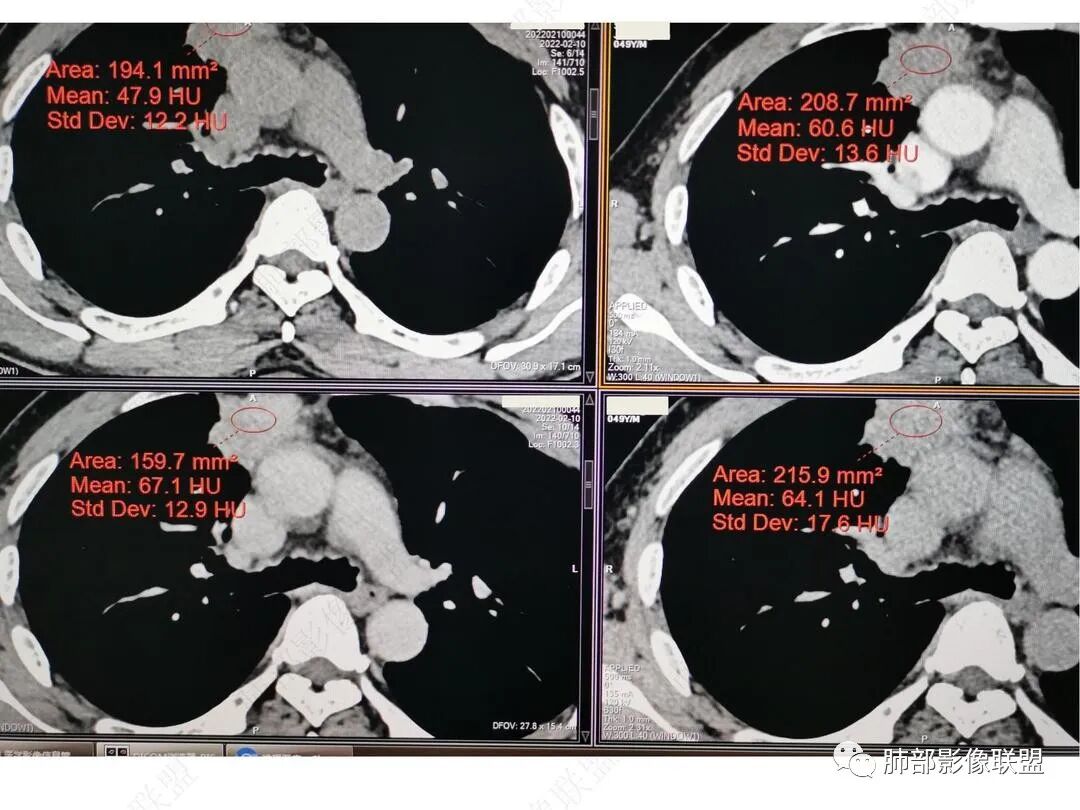

CT值信息

男,49,低热3月。胸部CT:右肺上叶前段纵隔旁见团片影,部分边缘毛糙,部分平直、内收,邻近卫星灶、晕征,重建L征?支气管管壁增厚、进入后堵塞;纵隔可见肿大淋巴结;病灶密度较均匀,中度强化。肝脏片状低密度影,边缘模糊。考虑炎性病变,PC?TB?鉴别腺癌。

中年男性,反复低热3月伴近期乏力及右上腹隐痛,白细胞,中性粒及淀粉样蛋白A增高,PCT不高,IGA、IGg增高,类风湿因子增高,未提供IGg4水平,影像改变,左侧肋骨陈旧性骨折(2020年已存在)右上叶前段胸骨旁的胸膜下新发病灶,支气管进入后一段才堵塞,肺动脉进入,走行自然,未见破坏,明显均匀强化,气管及支气管壁有增厚,钙化,纵隔内淋巴结增大,均匀强化,无坏死,纵隔内脂肪混浊,局部强化,肝内低密度灶,延迟强化(肺内病灶,淋巴结、混浊脂肪,肝内病灶强化均一致,且均为延迟强化)。初步考虑:免疫相关性炎症,IGg4相关炎症可能大,依据:IGA、IGg增高(未提供IGg4,可能是故意隐藏了),类风湿因子增高,炎性指标增高,但PCT不高,细菌感染可能就变小,加上病变同时累及肺、纵隔淋巴结,纵隔内脂肪、肝。

强化与肌肉类似,纵隔淋巴结强化类似

肝脏病变明确,是轻度强化,延迟强化特点,边缘模糊,有轻微的包膜挛缩。